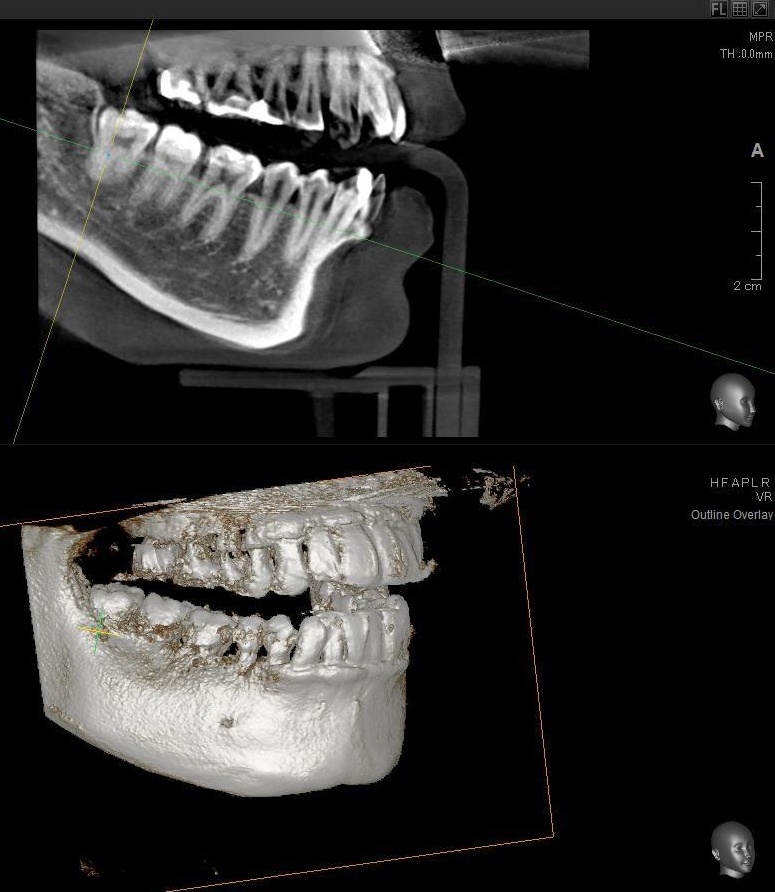

さらに、下顎の親知らずは下歯槽神経に非常に近いところに生えている場合もあるため、CTも撮影し詳しい解析を行います。

親知らずが生えている位置が、神経に近い、あるいは神経に当たっている場合は、大きな病院に紹介する場合もあります。

親知らずの根っこは下歯槽神経から近い距離にありますが、抜歯は可能との診断でした。